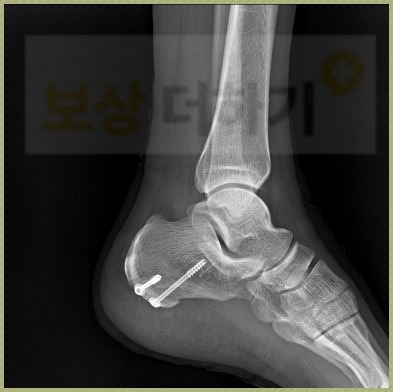

진단명: 종골의 골절, 폐쇄성 S9200 검사결과 종골이 골절되었음을 진단받았고, 수술적 치료가 불가피하였습니다.

image

뼈의 정복 및 내고정술을 하여 유합이 잘 되도록 하였습니다.